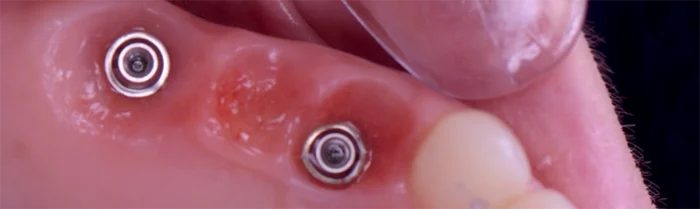

Implant

- Élément de liste #1

- Élément de liste #1

- Élément de liste #1

- Élément de liste #1